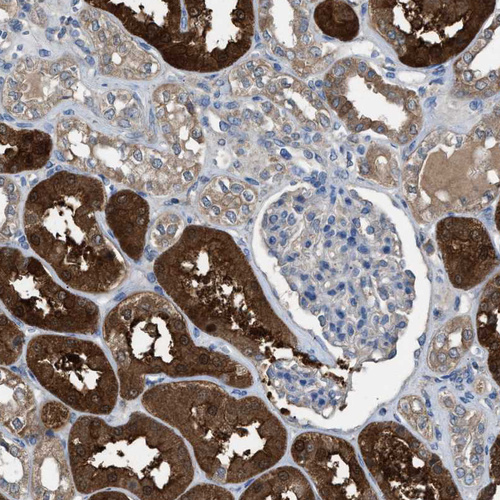

Immunohistochemistry analysis in human kidney and urinary bladder tissues using HPA021332 antibody. Corresponding NQO2 RNA-seq data are presented for the same tissues.